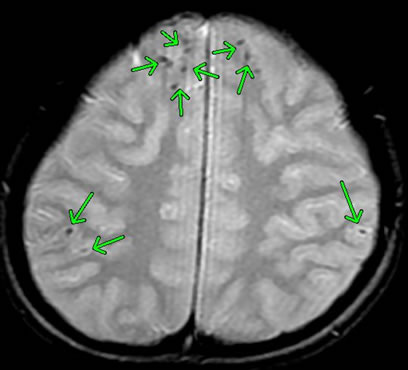

交通事故によって「脳挫傷」「頭蓋底骨折」「急性硬膜下血腫」「外傷性くも膜下出血」「びまん性軸索損傷」を発症した方の画像です。

脳表面の点状出血が広がると、「びまん性軸索損傷(びまんせいじくさくそんしょう)」となります。